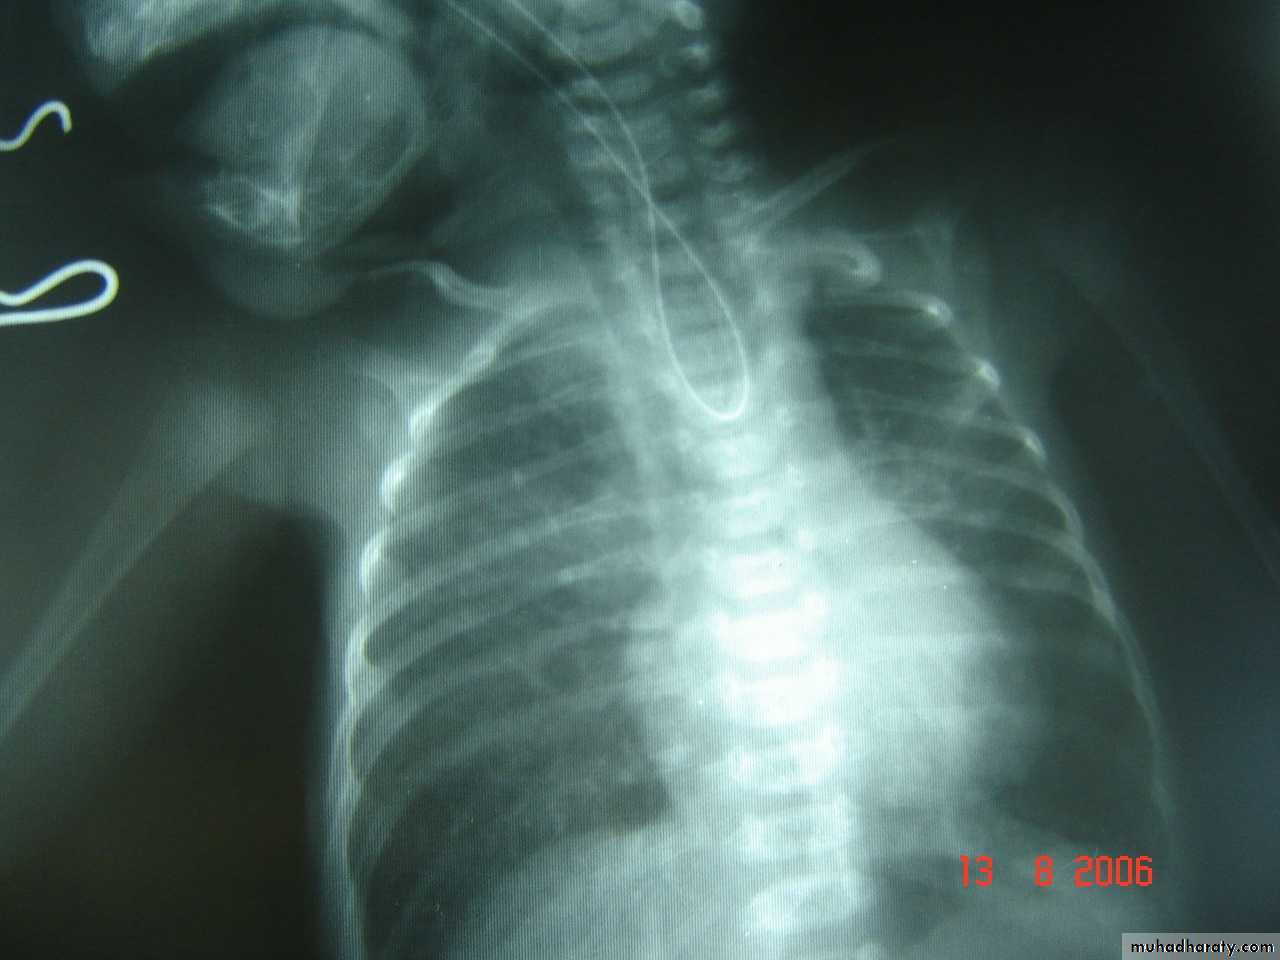

Scaphoid abdomen

Subcostal incision